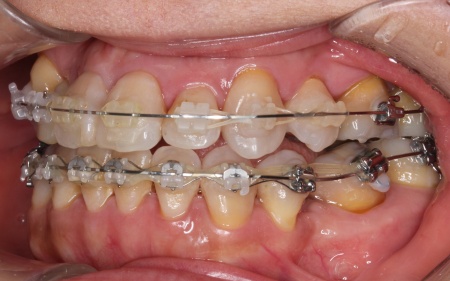

治療中

今回は審美性に配慮し、前歯には目立ちにくい透明のブラケットを、奥歯には耐久性のある金属製のブラケットを使用するハイブリッド矯正を選択しました。

ワイヤー矯正を進めていくなかで、右上の前歯2本(中切歯、側切歯)が骨の中で根がくっついている癒合歯(ゆごうし)であることが判明しました。

この影響で、側切歯の位置がずれたまま中切歯と一緒に動いてしまい、単独での正確な位置調整が難しい状態です。

そのため患者様と相談し、側切歯の表側に歯科用プラスチックを盛って見た目を整え、噛み合わせに支障が出ないよう慎重に調整を行う措置をとりました。

また歯を効率よく動かすため、顎の骨に矯正用の小さなネジであるインプラントアンカーを埋め込み、それを固定源とすることでしっかりと歯を動かしながら、歯列と噛み合わせのバランスを整えています。